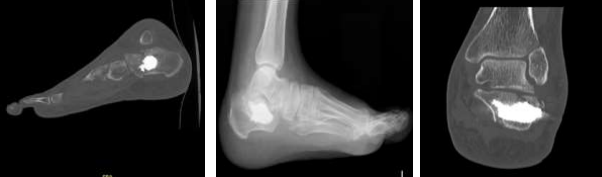

Radiographic assessment confirmed the diagnosis of an intra-articular calcaneal fracture. This was characterized by disruption of the Bohler angle and an increase in the Gissane angle, suggestive of posterior facet height loss (Figures 1 and 2). No extension into the calcaneocuboid joint was identified.

A computed tomography (CT) scan was performed to delineate the precise fracture anatomy, classify the fracture pattern according to the Sanders system, and inform treatment strategy.

The CT images revealed a Sanders type IV fracture, characterized by three fracture lines and four main posterior facet fragments (Figures 3 and 4). This complex fracture pattern demonstrates disruption of both the intra-articular and extra-articular components of the calcaneus. Furthermore, the crucial angle of Gissane measured approximately 165 degrees (Figure 5). This value significantly exceeds the normal range of 115-145 degrees, indicating significant posterior facet height loss and a potential for compromised joint congruity and long-term functional outcomes.